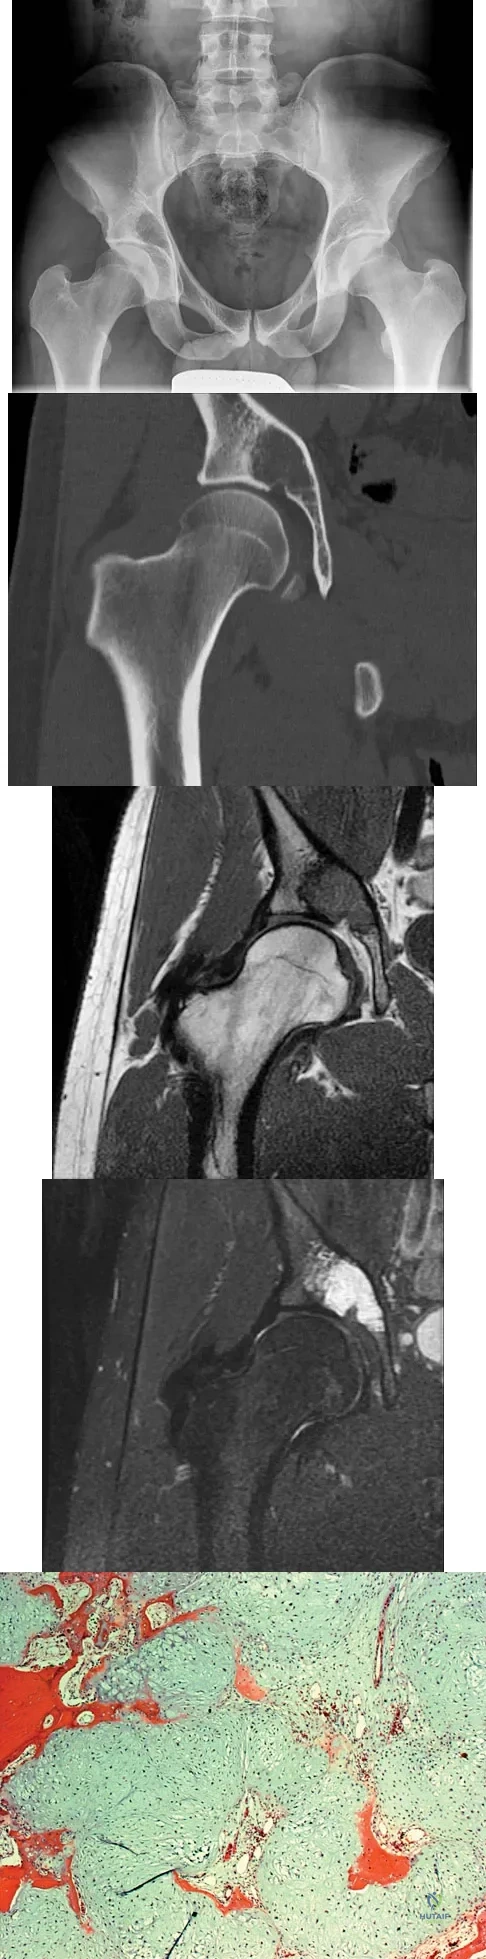

Question 33:

A 65-year-old man has a painful mass of the middle finger. A clinical photograph, lateral radiograph, coronal MRI scan, and biopsy specimen are seen in Figures 20a through 20d. What is the most likely diagnosis?

Options:

- Giant cell tumor

- Chondrosarcoma

- Osteosarcoma

- Infection

- Paget's disease

Correct Answer: Chondrosarcoma

Explanation:

Although the degeneration of an isolated benign cartilaginous lesion into a chondrosarcoma is rare, it occurs in roughly 10% of patients with Ollier's disease. Pain is the most common symptom of chondrosarcoma. The treatment of low-grade chondrosarcoma ranges from intralesional excision to wide amputation. The intent of the surgery is to remove all the disease to decrease the chance of local recurrence. Lee FY, Mankin HJ, Fondren G, et al: Chondrosarcoma of bone: An assessment of outcome. J Bone Joint Surg Am 1999;81:326-338.